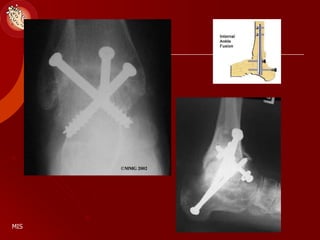

Diabetic Charcot Arthropathy

RELOCATION ARTHRODESIS